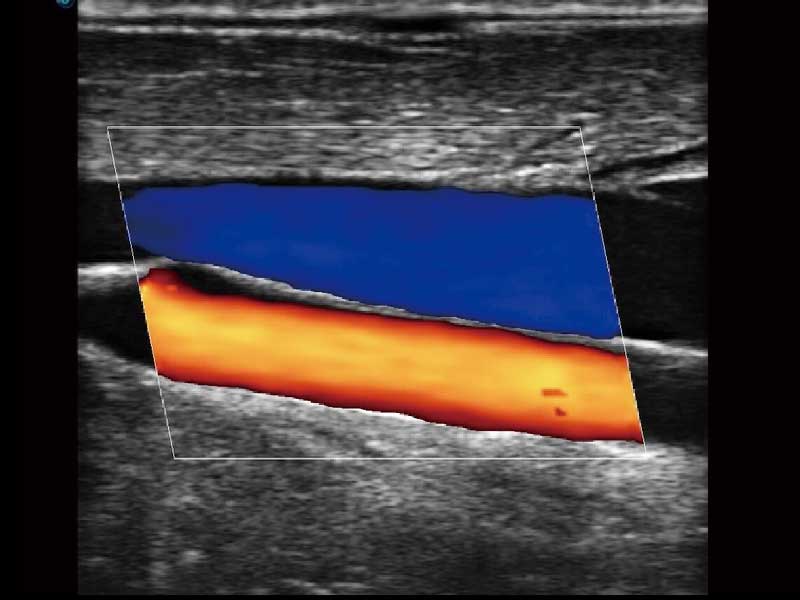

E2便携式彩色多普勒超声诊断系统采用专业的超声技术平台、高度集成化的硬件模块和结构设计、简便的操作流程、多探头接口设计,兼顾了优质图像、轻便机身以及台便两用的临床使用需求。

• 高端成像技术

μ-Scan微米成像、空间复合成像、高分辨率血流成像。

临床图